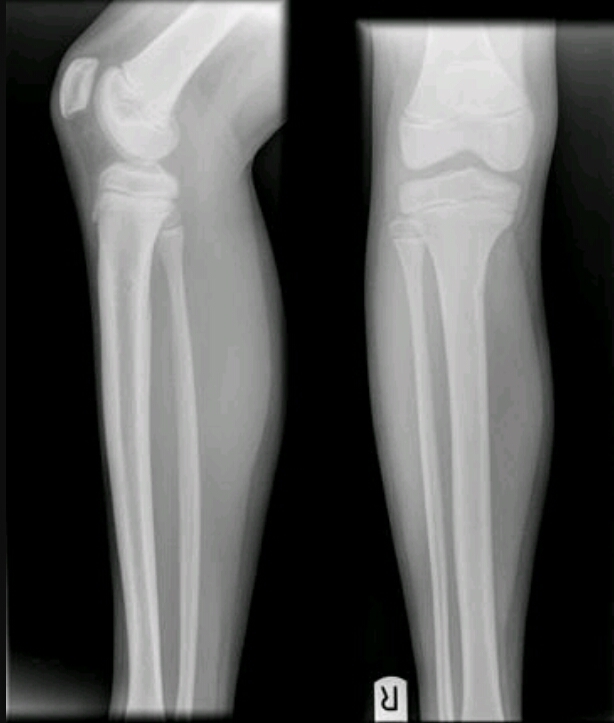

Findings? Diagnosis?

Geographic, central, oval radiolucency with long axis parallel to bone

POSSIBLE FALLEN FRAGMENT SIGN, OPEN GROWTH PLATES

Solitary bone cyst